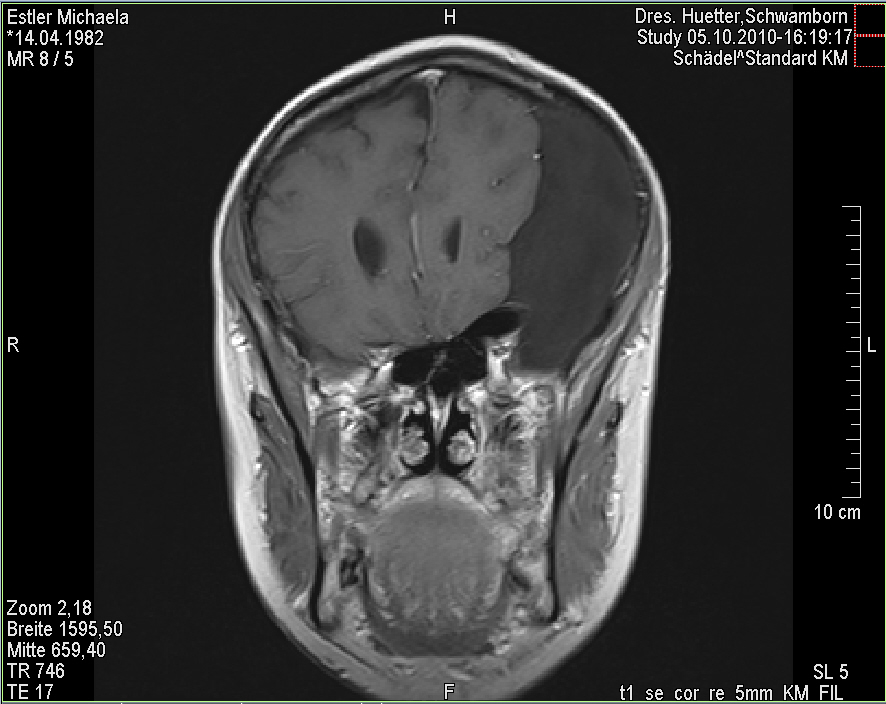

Ich stell euch hier noch eine kleine Galerie rein mit den neuesten Bildern. Ich denke es ist unübersehbar, dass das Ding gewachsen ist, außerdem mir meine komplette Hirnmittelline verschiebt und immer mehr Rücklagerung bekommt und Richtung Hirnsteuerungszentrum drückt. Meine häufiger auftretenden Stürze und Koordinationsprobleme werden also in naher Zukunft sicherlich nicht weniger werden und mein Doc und ich werden uns wohl auch zeitnah über eine weitere Klinik und eine mögliche weitere OP unterhalten müssen.